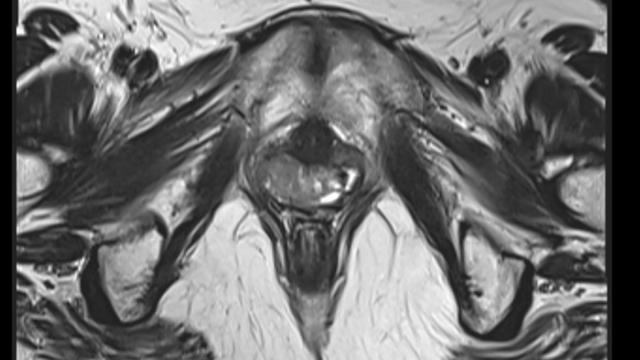

Crédito, Getty Images

Alguns examesroleta da sorteimagem ajudam a diagnosticar a síndrome